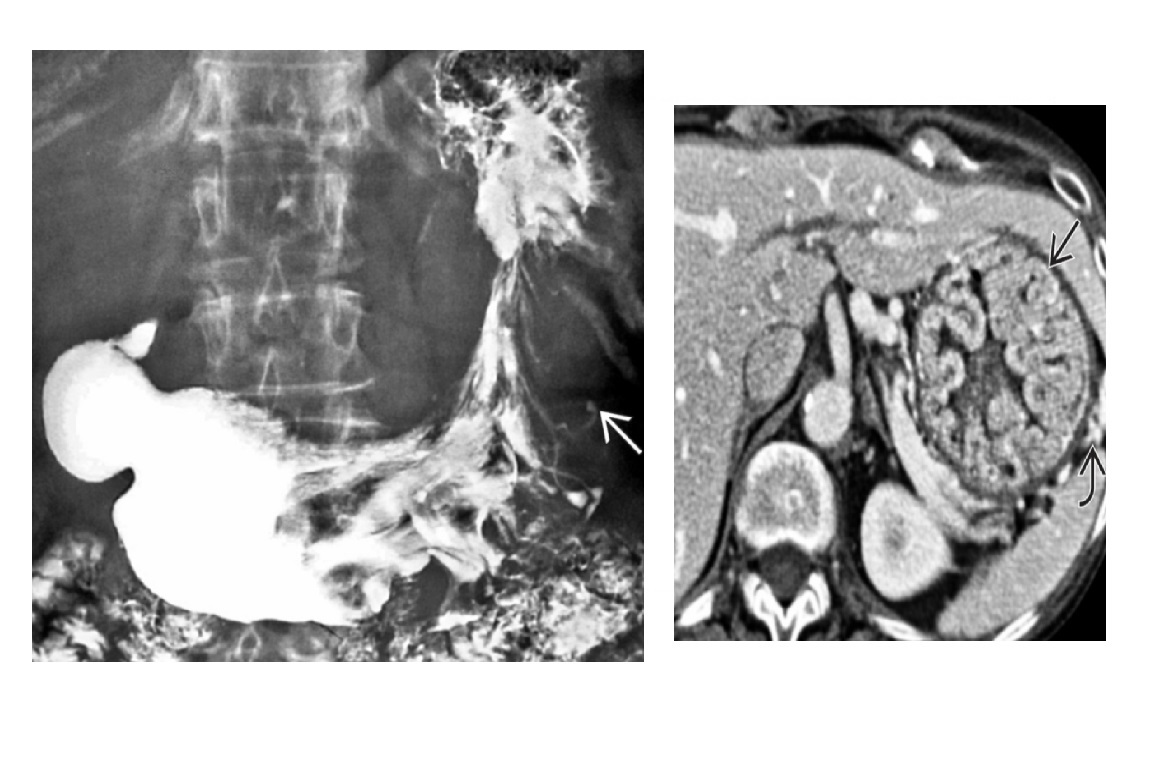

Carcinoid

spiculated mesenteric mass with calcification/ desmoplastic reaction

Tethering of SB loops

90% arise in terminal ileum/appendix

Hyper-vascular liver mets - Carcinoid syndrome

111I- Octreotide scans (1st - highest sensitivity)

or 123I-MIBG (for 10% dont take up octreotide)

for Dx and staging

Big centres use gallium PET

Assocaited with MEN 1 or MEN 2a

DDX

Sclerosing mesenteritis/ mesenteric pannicultuis

- FAT HALO sign - Mass envelop vessels, but preservation of fat around vessels

- usually jejunal small bowel mesentery

Gastrointestinal Stromal Tumor (GIST)

- Hypervascular tumor, not associated with desmoplastic effect on mesentery

Small Bowel Carcinoma

- More common in duodenum or jejunum than in ileum

- Causes luminal obstruction

- Mass and metastases are hypovascular